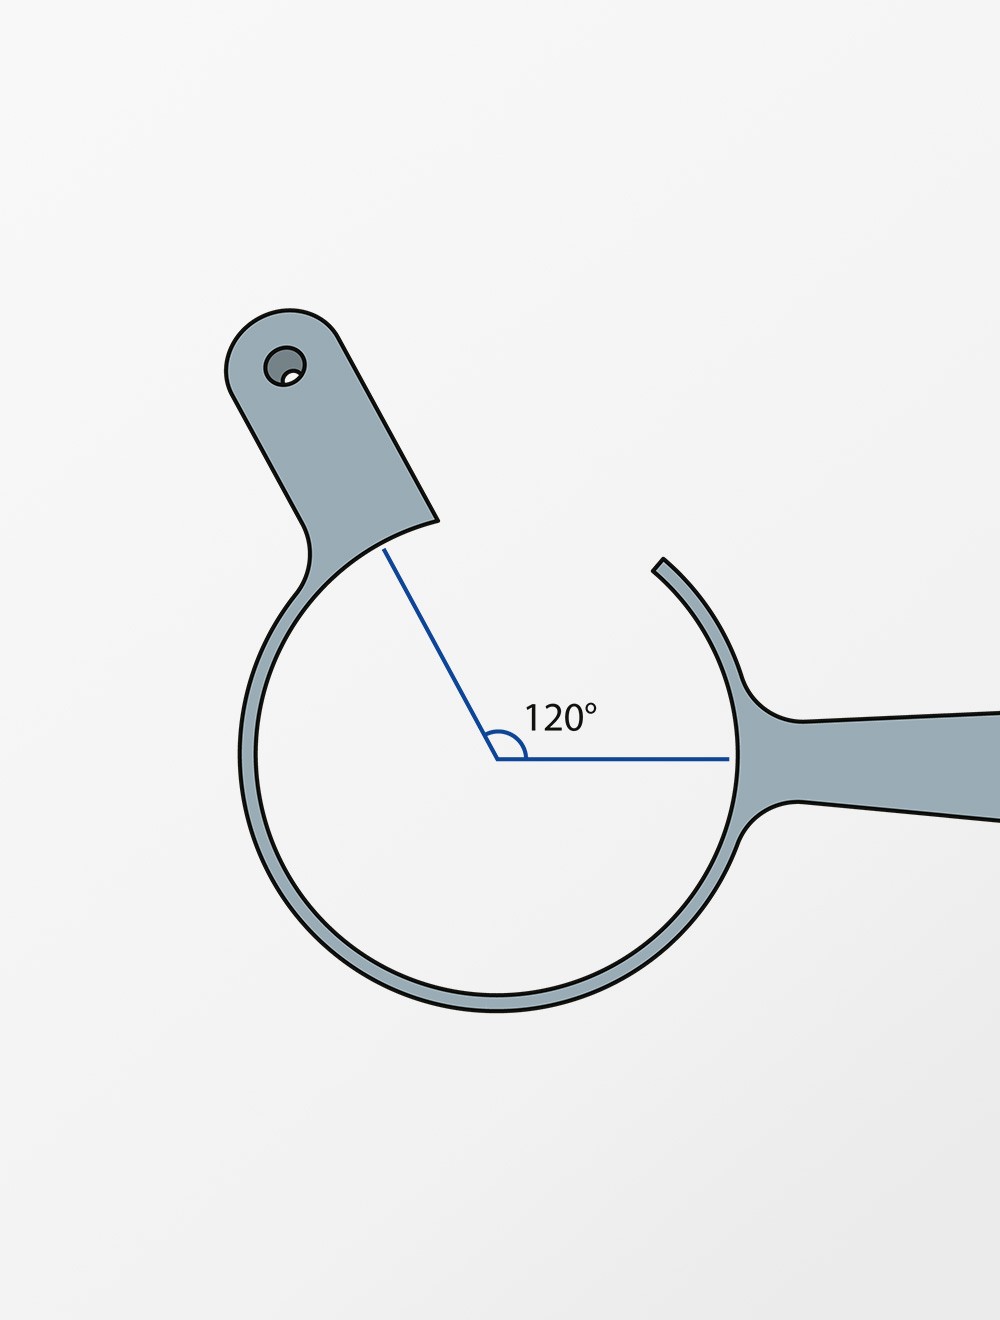

上松・土井氏硝子体内注射ガイド 左手保持 26G-30G×3/4“用

硝子体内注射を安全に行うための注射ガイドです。

About 01.

眼球固定リングに取り付けられた注射ガイドにより刺入部の位置計測が不要で、針の角度や深度を常に一定に保つことができます。そのため網膜や水晶体に損傷を与えることなく薬剤を網膜付近に到達させることができます。針を挿入したまま前房水除去ができるなどの利点があります。